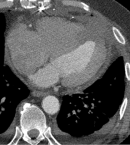

Follow-up and outcome of interventions: the patient was weaned from cardiopulmonary bypass without complications. Recovery was uneventful, with gradual improvement in symptoms, mobility, appetite, and resolution of dyspnea at rest. He was transferred to a cardiac rehabilitation unit, and repeated cardiac CT angiography confirmed successful repair (Figure 4).

Figure 4: postsurgical computerized tomography after left ventricular remodeling with xenopericardial patch (Dor Procedure); pericardial and bilateral pleural effusion present